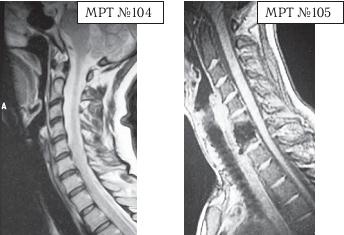

Приведённый ниже случай является показательным примером, как пациентка попала к недобросовестному хирургу, который сделал ей абсолютно необоснованную операцию.

На МРТ № 104 наблюдается начальная стадия дегенеративного процесса в шейном отделе позвоночника, протрузия межпозвонкового диска в сегменте CVI—CVII.

На МРТ № 105 наблюдается состояние после проведённой тотальной дискэктомии с передним межтеловым спондилодезом в сегменте CV—CVII, выпрямление физиологического лордоза, абсолютный стеноз спинномозгового канала с блоком ликворных путей, секвестрированные грыжи (с краниальной миграцией секвестров) в сегментах CIV-CV, CV-CVI, CVII-ThI.

Состояние пациентки после операции ухудшилось, а в течение последующего года — значительно усугубилось. В данном конкретном случае не совсем понятно, зачем сделали эту операцию? Дооперационные жалобы больной были больше сосудистого характера. Прямых показаний к операции просто не было! Если бы данная пациентка прошла медикаментозное лечение у невропатолога, без хирургического вмешательства, то сейчас её здоровье было бы намного лучше, да и будущее бы не вызывало опасений в плане последующих осложнений.